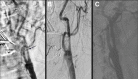

Acute carotid stent thrombosis

Carotid artery stenting is a method used in the treatment of extracranial carotid artery stenosis that is becoming increasingly more common. Acute carotid thrombosis following CAS is a very rare and devastating complication that can be lethal for the patient unless treated immediately. We report a case of acute carotid stent thrombosis occurring immediately after emergent revascularization, and that was treated with intraarterial tissue plasminogen activator and intravenous tirofiban infusion.

Figures

Figure 1

Figure 2